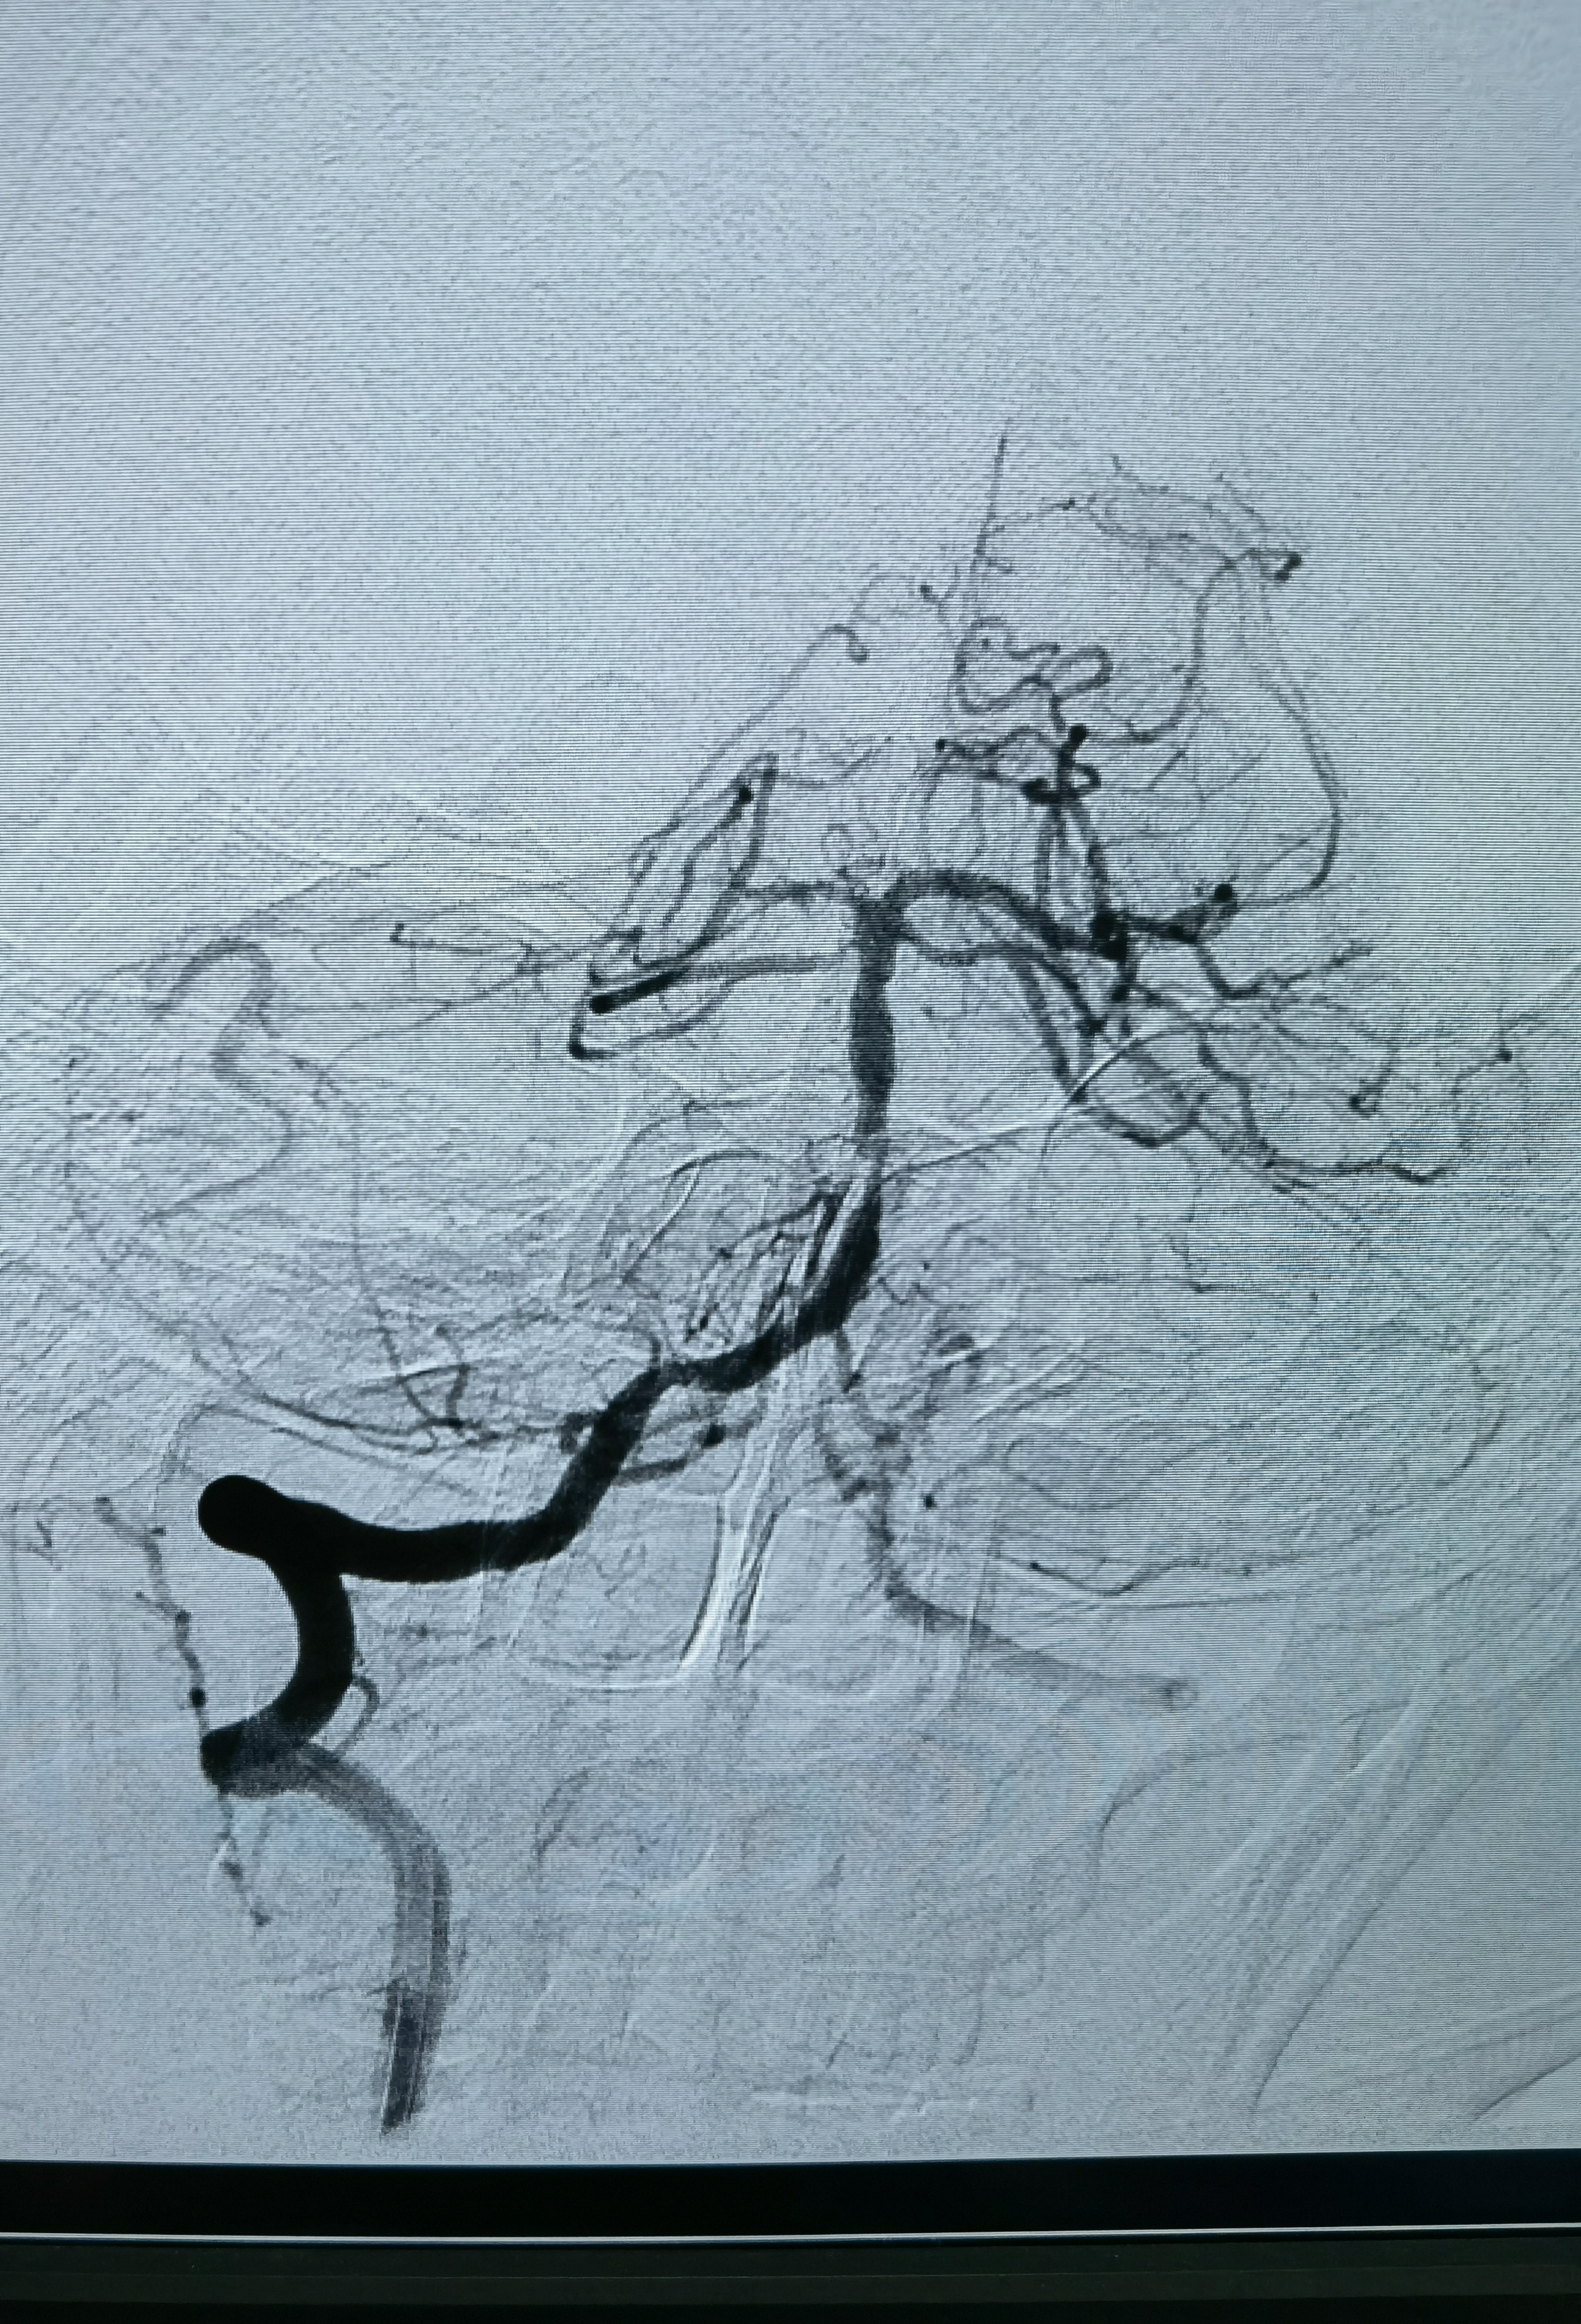

释放支架后造影

蒙片看支架打开贴壁良好

术后正位造影

术后侧位造影